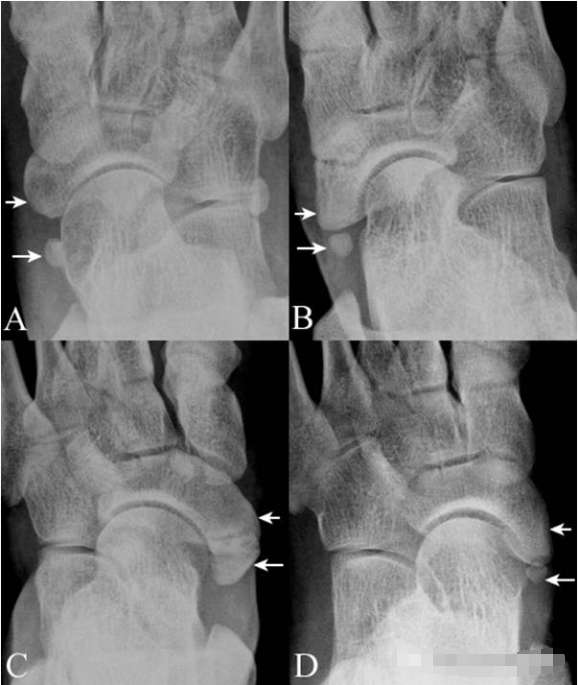

11.外胫骨:

舟骨粗隆(短箭)的后内侧可见形态不一的外胫骨(长箭),A图为 I 型, B图为 II 型, C图为 III 型。D图示在明显突出的舟骨粗隆后见外胫骨( II 型),融合后即为 III 型。外胫骨需与舟骨撕脱骨折鉴别,临床表现和周围软组织改变可提供依据。